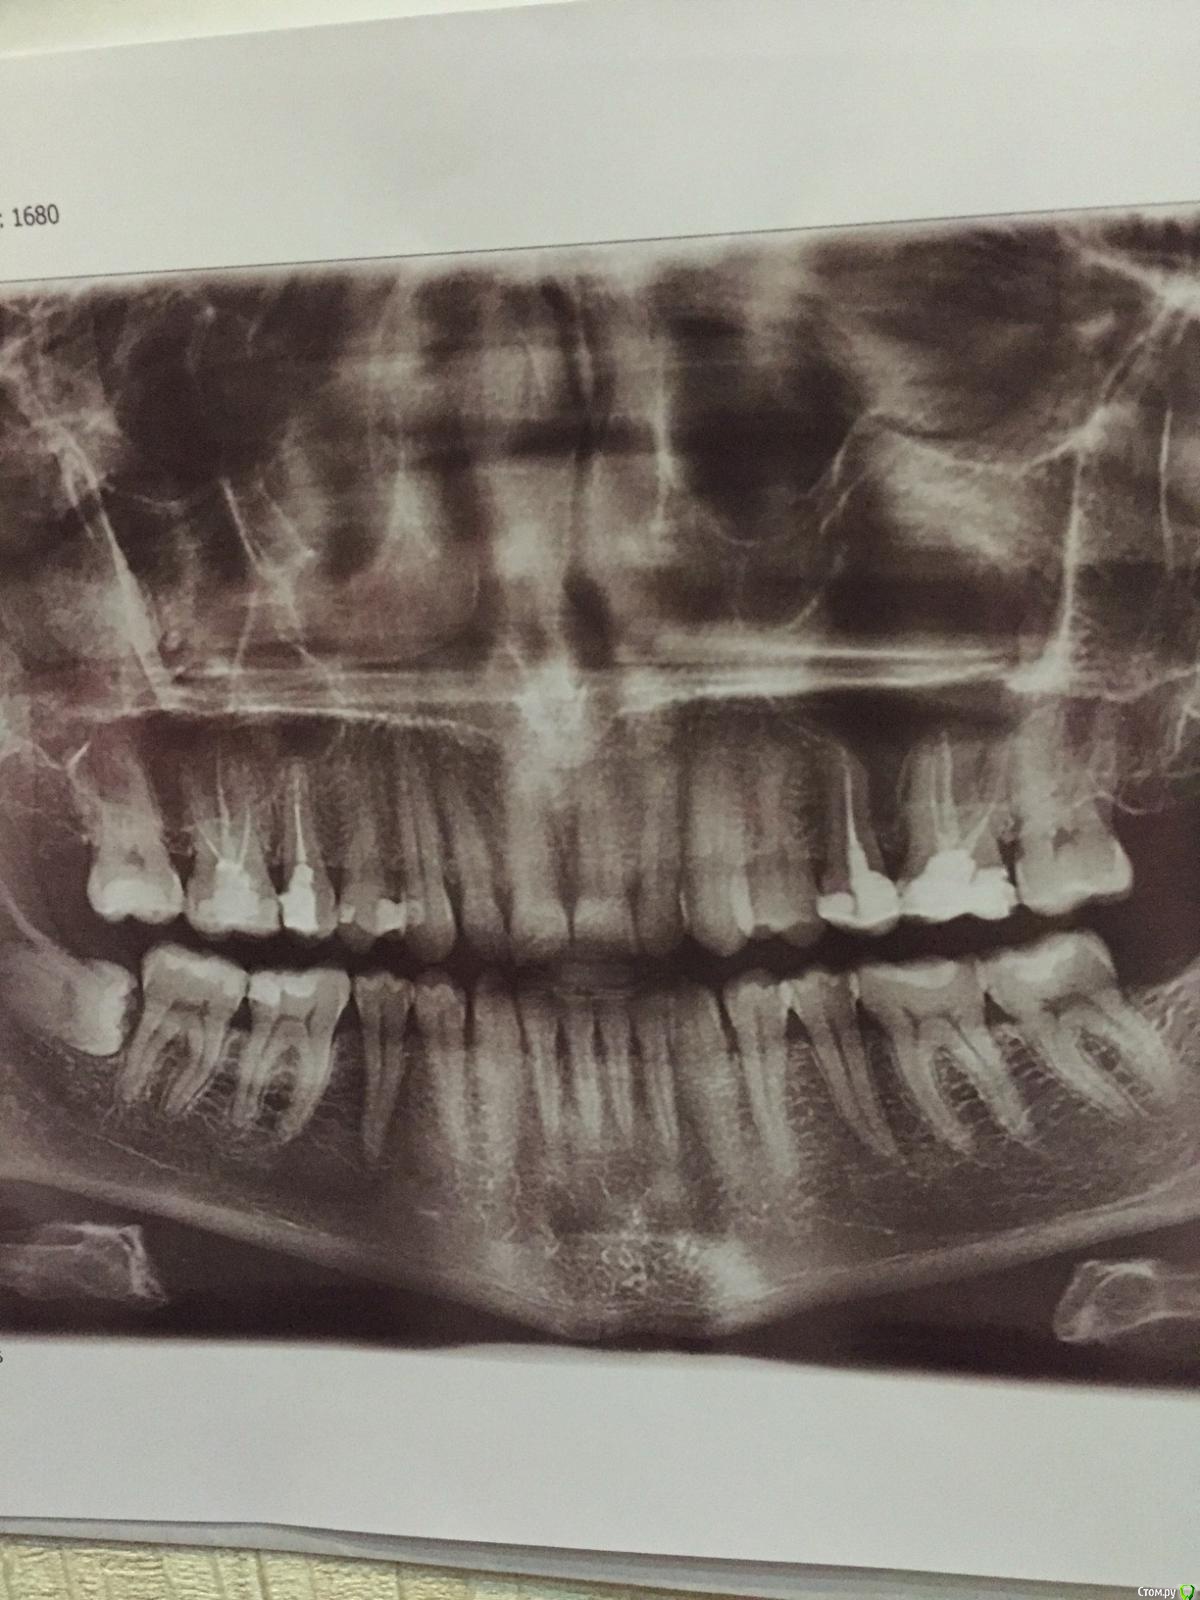

Andrey1307 Опубликовано 16 марта, 2016 Поделиться Опубликовано 16 марта, 2016 Доброго времени суток, уважаемые стоматологи. Что можете сказать по снимку? Какие Зубы требуют лечения? Беспокоит боль и реакция на холодное и горячее в 16 зубе. Ссылка на комментарий

IvanK Опубликовано 17 марта, 2016 Поделиться Опубликовано 17 марта, 2016 Повторное лечение 16,15,25,26, далее протезирование коронкамиЛечение 14,17, 46,47 контактный пунктудаление 48.... Ссылка на комментарий

pils Опубликовано 17 марта, 2016 Поделиться Опубликовано 17 марта, 2016 Спасибо. А что значит контактный пункт?Зубы контактируют своими поверхностями друг с другом - эти контакты и имел в виду доктор. Там у Вас указанные зубы не имеют правильного контакта - возможно, что кариес в 46 - следствие этого. Ссылка на комментарий

IvanK Опубликовано 18 марта, 2016 Поделиться Опубликовано 18 марта, 2016 Зубы контактируют своими поверхностями друг с другом - эти контакты и имел в виду доктор. Там у Вас указанные зубы не имеют правильного контакта - возможно, что кариес в 46 - следствие этого. да Ссылка на комментарий